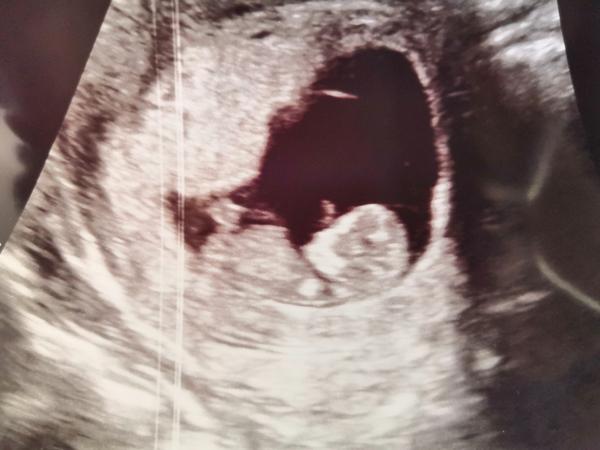

ja som bola na prvej kontrole v cca 10 týždni a mám hneď fotku ako mi "kýva" 🤷🏼♀️

@uzivatelka1113 jeeej to je nádherne ❤️ Fotku nepridas? 🥰